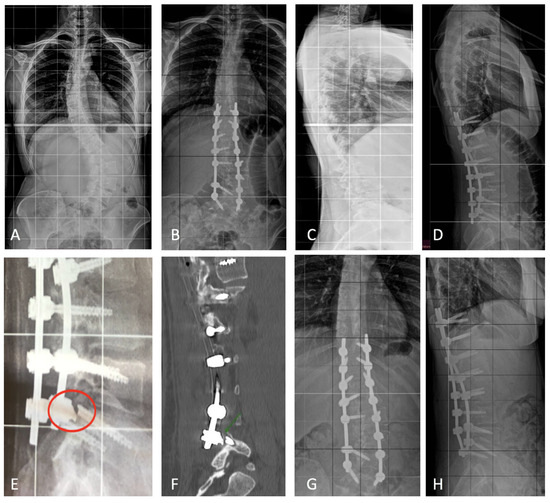

3.4. Complications